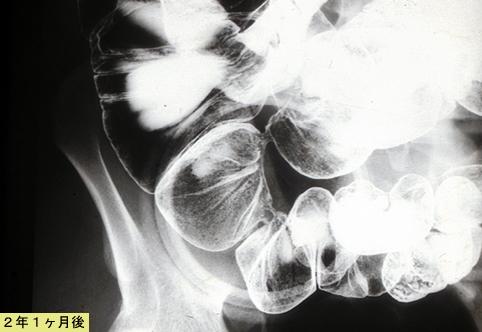

Criteria of Hist.ClassificationInflammatory or ulcerative disease / lesions/Crohn disease

LocationSmall intestine/Jejunum

Technique, MethodX-ray